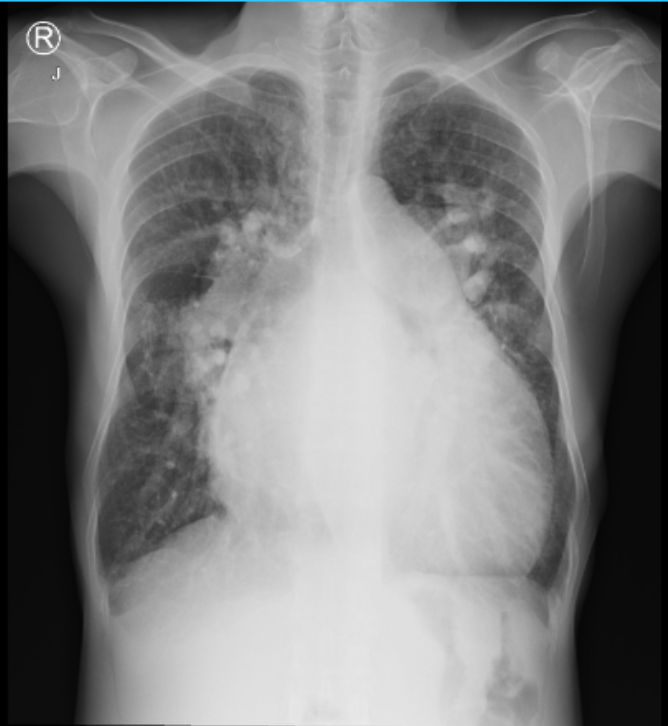

Gambar Xray pasien

Kasus: Laki laki usia 55 tahun dengan kasus hernia inguinalis lateralis dekstra reponible dengan ASD dan hipertensi pulmonal derajat sedang. Pasien dilakukan insersi epidural kateter di L4-L5 setelah di konfirmasi dengan loss of resistance dengan saline dan test dose. Regimen epidural yang diberikan bupivacaine 0,25% + lidocaine 1% volume 10 mL. Intraoperatif diberikan titrasi norepinephrine dengan dosis titrasi 0,15-0,3 mcg/kgBB/menit dan tirasi dobutamine 2,5-5 mcg/kgBB/menit. Pengobatan postoperatif analgesia pengobatan epidural bupivacaine 0,0625% + morfin 0,5 mg volume 10 mL tiap 12 jam, dan parasetamol 500 mg tiap 6 jam tablet untuk obat analgesia.

Pembahasan: Teknik anestesi epidural dipilih karena memiliki onset yang lebih lama dan hemodinamik variasi yang lebih kurang dibandingkan dengan teknik anestesi spinal atau kombinasi teknik spinal-epidural. Sedangkan teknik general anestesi tidak dipilih karena berisiko terhadap resistensi vaskular pulmonal dan dapat mengubah arah shunting. Prinsip dari penanganan ASD adalah untuk mempertahankan cardiac output dan menghindari adanya penurunan dari resistensi sistemik vaskular. Mempertahankan resistensi sistemik vaskular berdsarkan dengan mean arterial pressure sehingga menghindari adanya perubahan arah shunt.